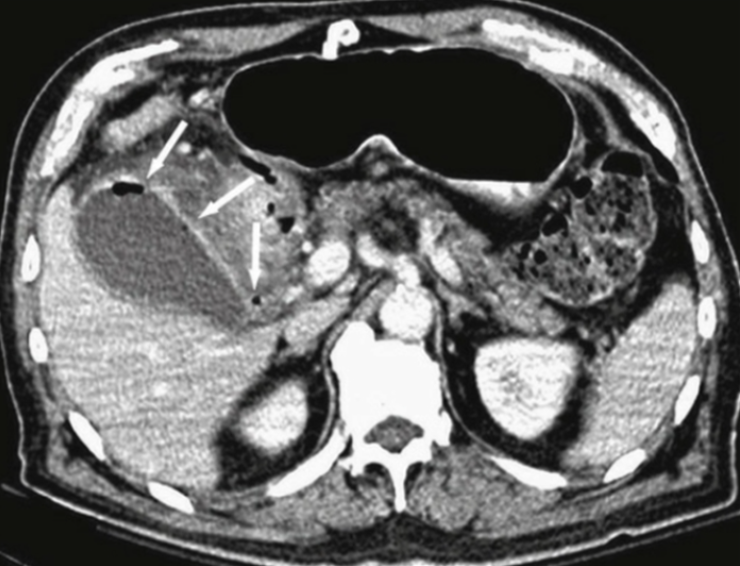

TOMOGRAFIA DE ABDOMEN COM CONSTRASTE VENOSO .

MASSA RETROPERITONEAL A DIREITA QUE COMPRIME AS VISCERAS A DIREITA , A QUAL NÃO INVADE AS ESTRUTURAS. PRESENÇA DE CAPTAÇÃO HETEROGENEA DO CONSTRASTE NA PERIFERIA

ASPECTO DE SARCOMA PERITONEAL.